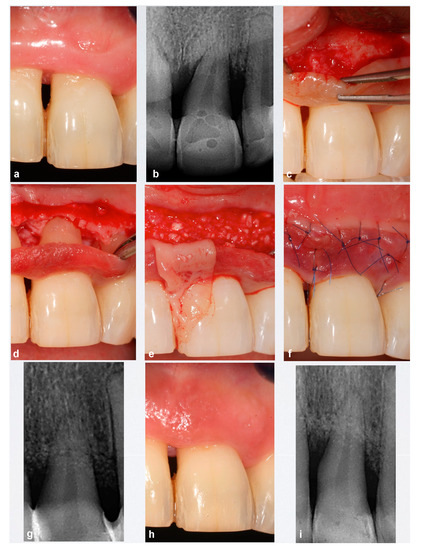

Interimplant Papilla Reconstruction in the Esthetic Zone。Interdental Papilla Reconstruction Surgery - Advanced。sddefault.jpg。「乳頭再建 = Papilla reconstruction」山口文誉 / 鈴木真名 / 髙橋雅仁定価: ¥ 14000裁断済みです。Dr.夏秋の臨床図鑑 虫と皮膚炎 改訂第2版。。書き込みはありません。#山口文誉 #鈴木真名 #髙橋雅仁 #本 #自然/医療・薬学・健康